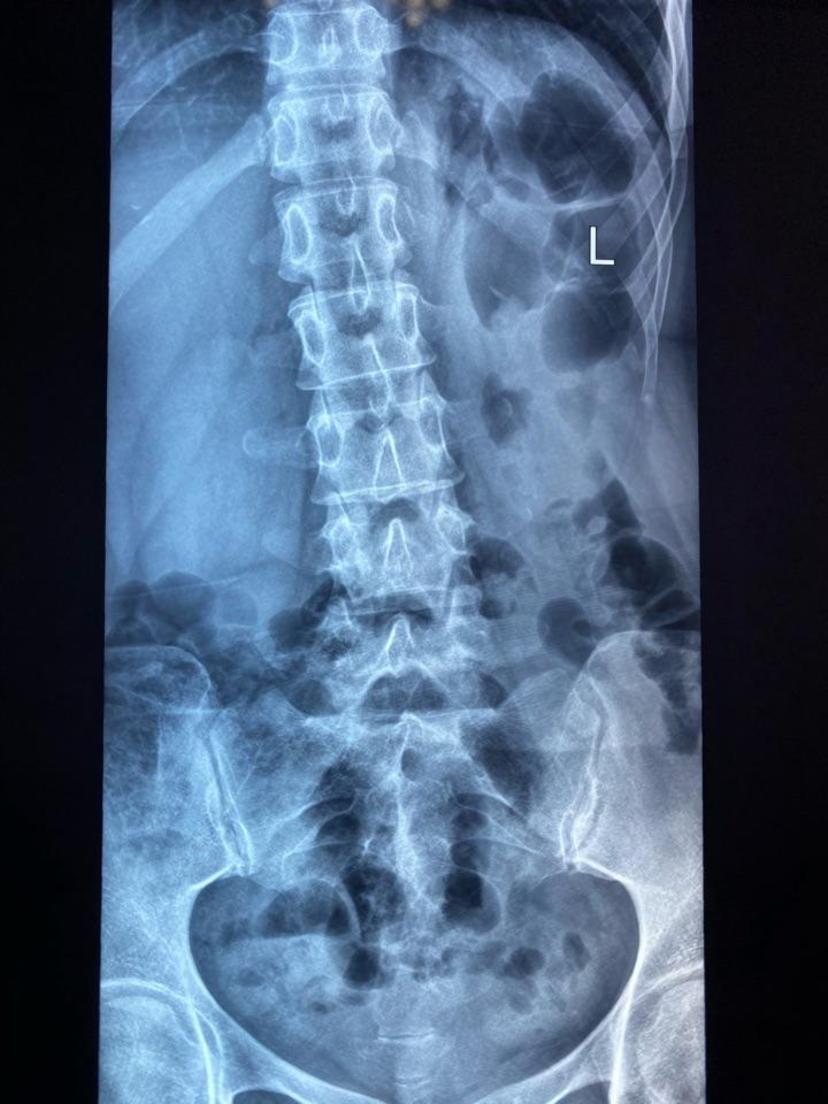

患者左侧腰腿痛、左下肢麻木,行走困难,行椎间孔镜微创手术,术程半小时顺利取出压迫神经的髓核组织,即刻疼痛麻木症状消失,术后次日正常下地走路,开心出院!左下肢疼痛麻木导致的姿势性侧弯